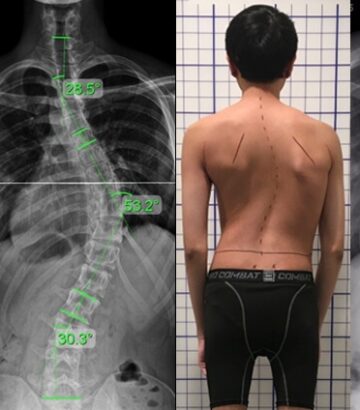

الفرق بين اعوجاج العمود الفقري العلوي والسفلي | كيف يختلف في الأعراض والعلاج؟…

الفرق بين اعوجاج العمود الفقري العلوي والسفلي | كيف يختلف في الأعراض والعلاج؟ يُعد اعوجاج العمود الفقري عند المراهقين من أكثر المشكلات شيوعًا التي يلاحظها الأهل عندما يبدأ ظهر الطفل أو المراهق في الميلان